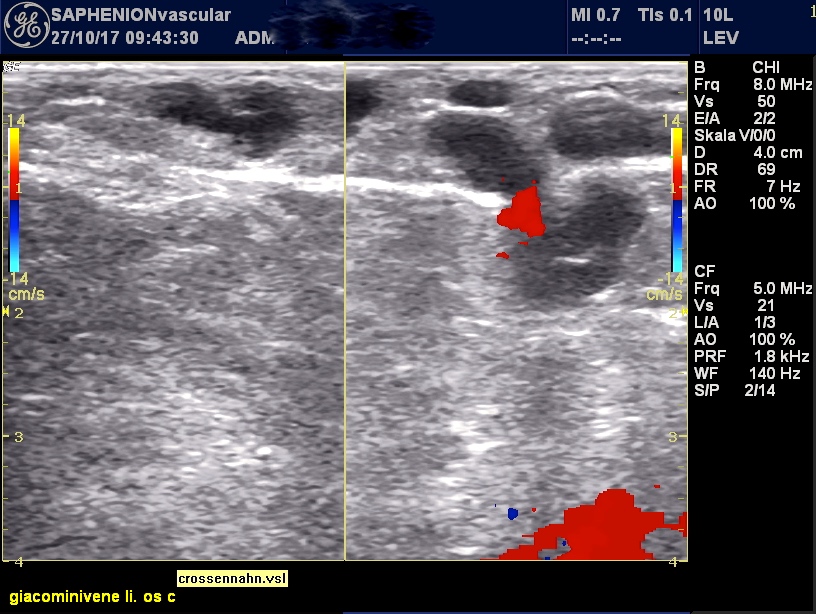

Saphenion®: Venenkleber und Mikroschaum simultan? Zustand nach Verklebung eines Aneurysmas und gleichzeitiger Mikroschaumtherapie von Seitenästen

Post operativer Ultraschall zeigt Verschluss der venösen Erweiterungen bis an die Einmündung in die Knievene heran, auch die mit Mikroschaum behandelten Venen sind verschlossen.

Post-operative ultrasound shows the closure of ectatic parts until the popliteal junction and also the closure of side branches after microfoam therapy.